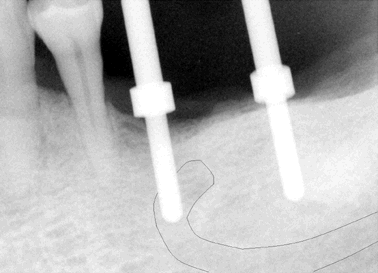

Fig.1 38 year-old male patient presented in 2006 with chief complaint "loose bridges". Exam shows poor oral hygiene and restoration, and advanced periodontal disease. Initial treatment includes removal of grossly nonsalvageables, scaling & root planing, and upper removable partial using #1 as distal abutment. Due to pneumatic sinuses and finance, implants would be placed in the mandible first. | |

Fig.2 High looped mental nerve is noted pre-op. To avoid potential damage to the nerve, local infiltration was used. Flap was raised to expose the mental nerve before osteotomy. A shorter implant was chosen for #29 (5x6mm), as compared to 5x8 implants (Bicon) for #28 and 30. The depth of osteotomy for #29 was controlled so as not to pass below the mental foramen, but still to bury implant platform. According to manufacture manual, the implant should be buried 2-3 mm below the ridge. No paresthesia was found post-op, although #29 implant was apparently on the top of the mental nerve (red tracing line). As shown below by cone-beam, the apex of this implant must be located lingual to the mental nerve when the latter exits the mental foramen. The drawback is that a few of threads was exposed buccally for #29 implant (not shown), probably because it was not buried deep enough. The thread exposure was found during uncovering, 4 months after placement. No further treatment was pursued for thread exposure. Integrated abutment crowns were placed for #28-30. This panorex was taken 1.5 years after crown placement. Radiographically, implant thread is below the alveolar ridge. Twenty eight months since functioning, these 3 implant-supported crowns have been stable with healthy bone and gingiva. | |